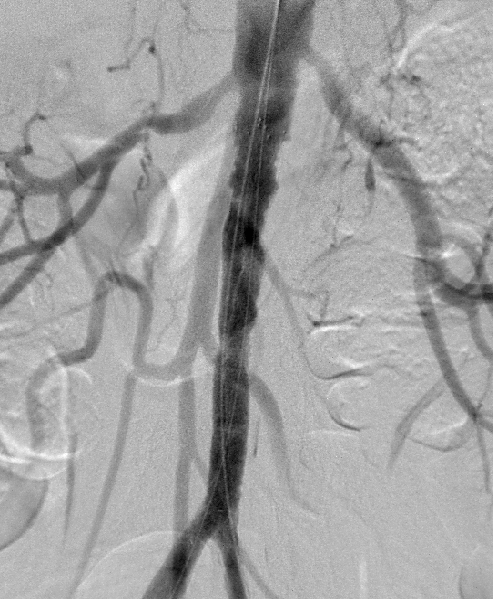

男性、58岁,间跛100米、慢性下肢缺血,病史3年

造影提示患者为长段闭塞,如果一期行腔内治疗,则累及肾动脉;所以行预置导管溶栓,后行支架术,血流重建效果显著。